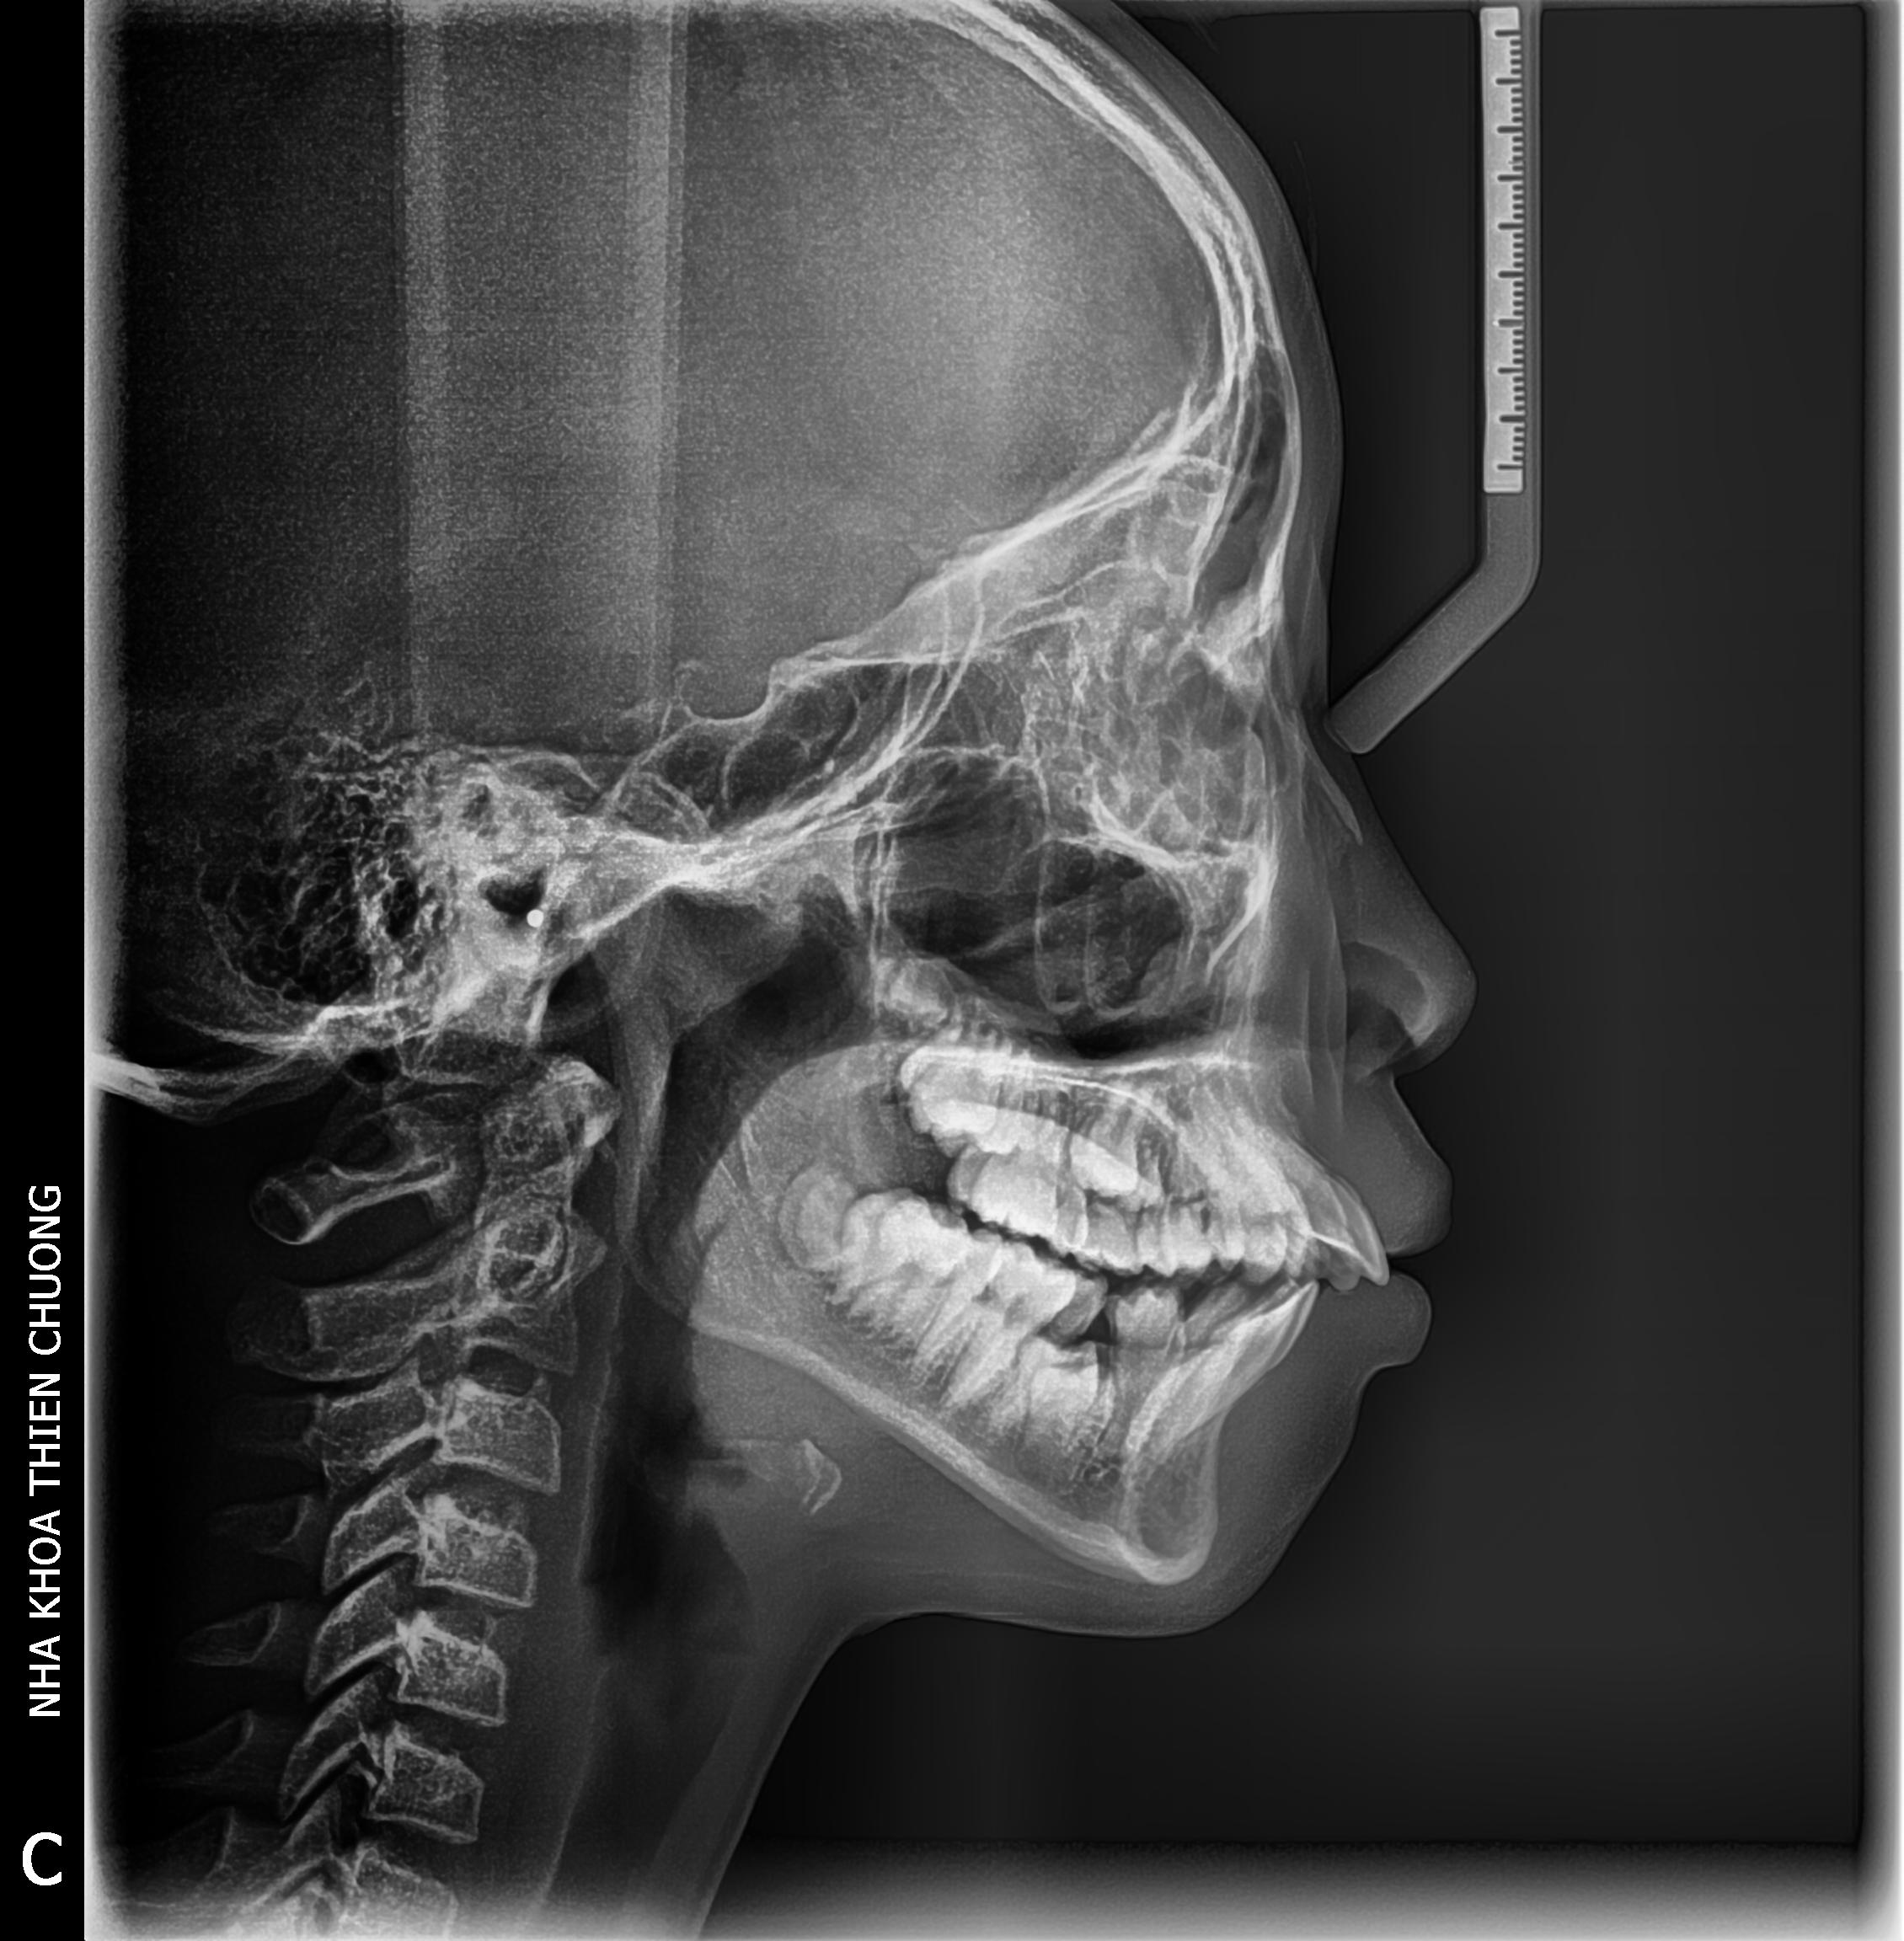

+ Phim X – quang sọ nghiêng: cho hình ảnh về tình trạng

xương sọ mặt, rất cần thiết trong chỉnh hình răng hàm mặt như niềng răng.